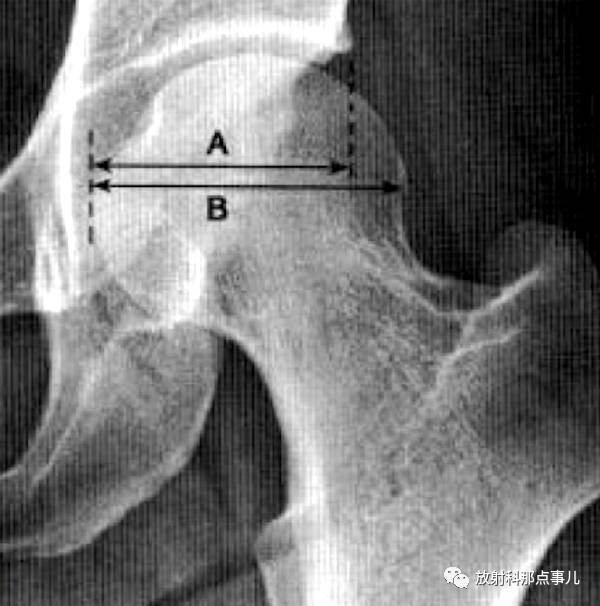

股骨头受髋臼覆盖部分的横径除以股骨头的横径,正常时应大于0.75.